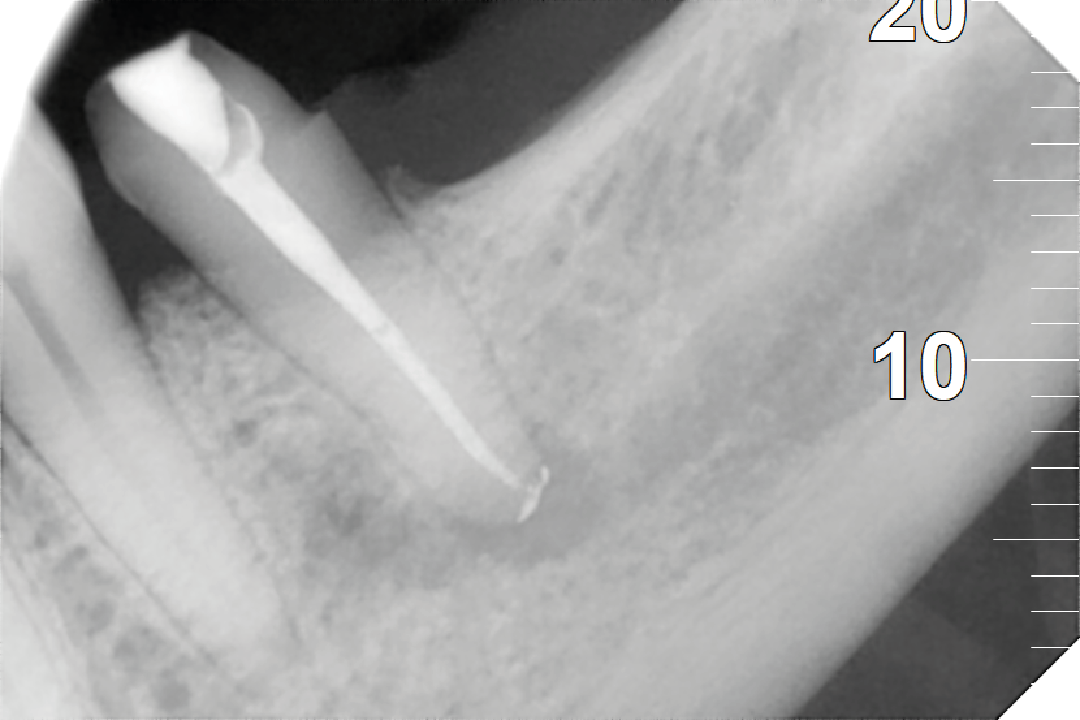

Se realiza con anestesia local y comienza con un aislamiento absoluto, para impedir la contaminación de saliva, limpiamos la cavidad hasta llegar a la cámara pulpar donde ubicamos los conductos radiculares y donde se inicia el proceso de desinfección y limpieza de todas las bacterias, hasta que los rellenamos con un material biocompatible que produce un sellado hermético en la entrada de cada uno.

Por último, se hace la restauración definitiva, que dependerá de la cantidad de tejido que quede (desde una reconstrucción, una incrustación o una corona, devolviendo la función a la pieza.